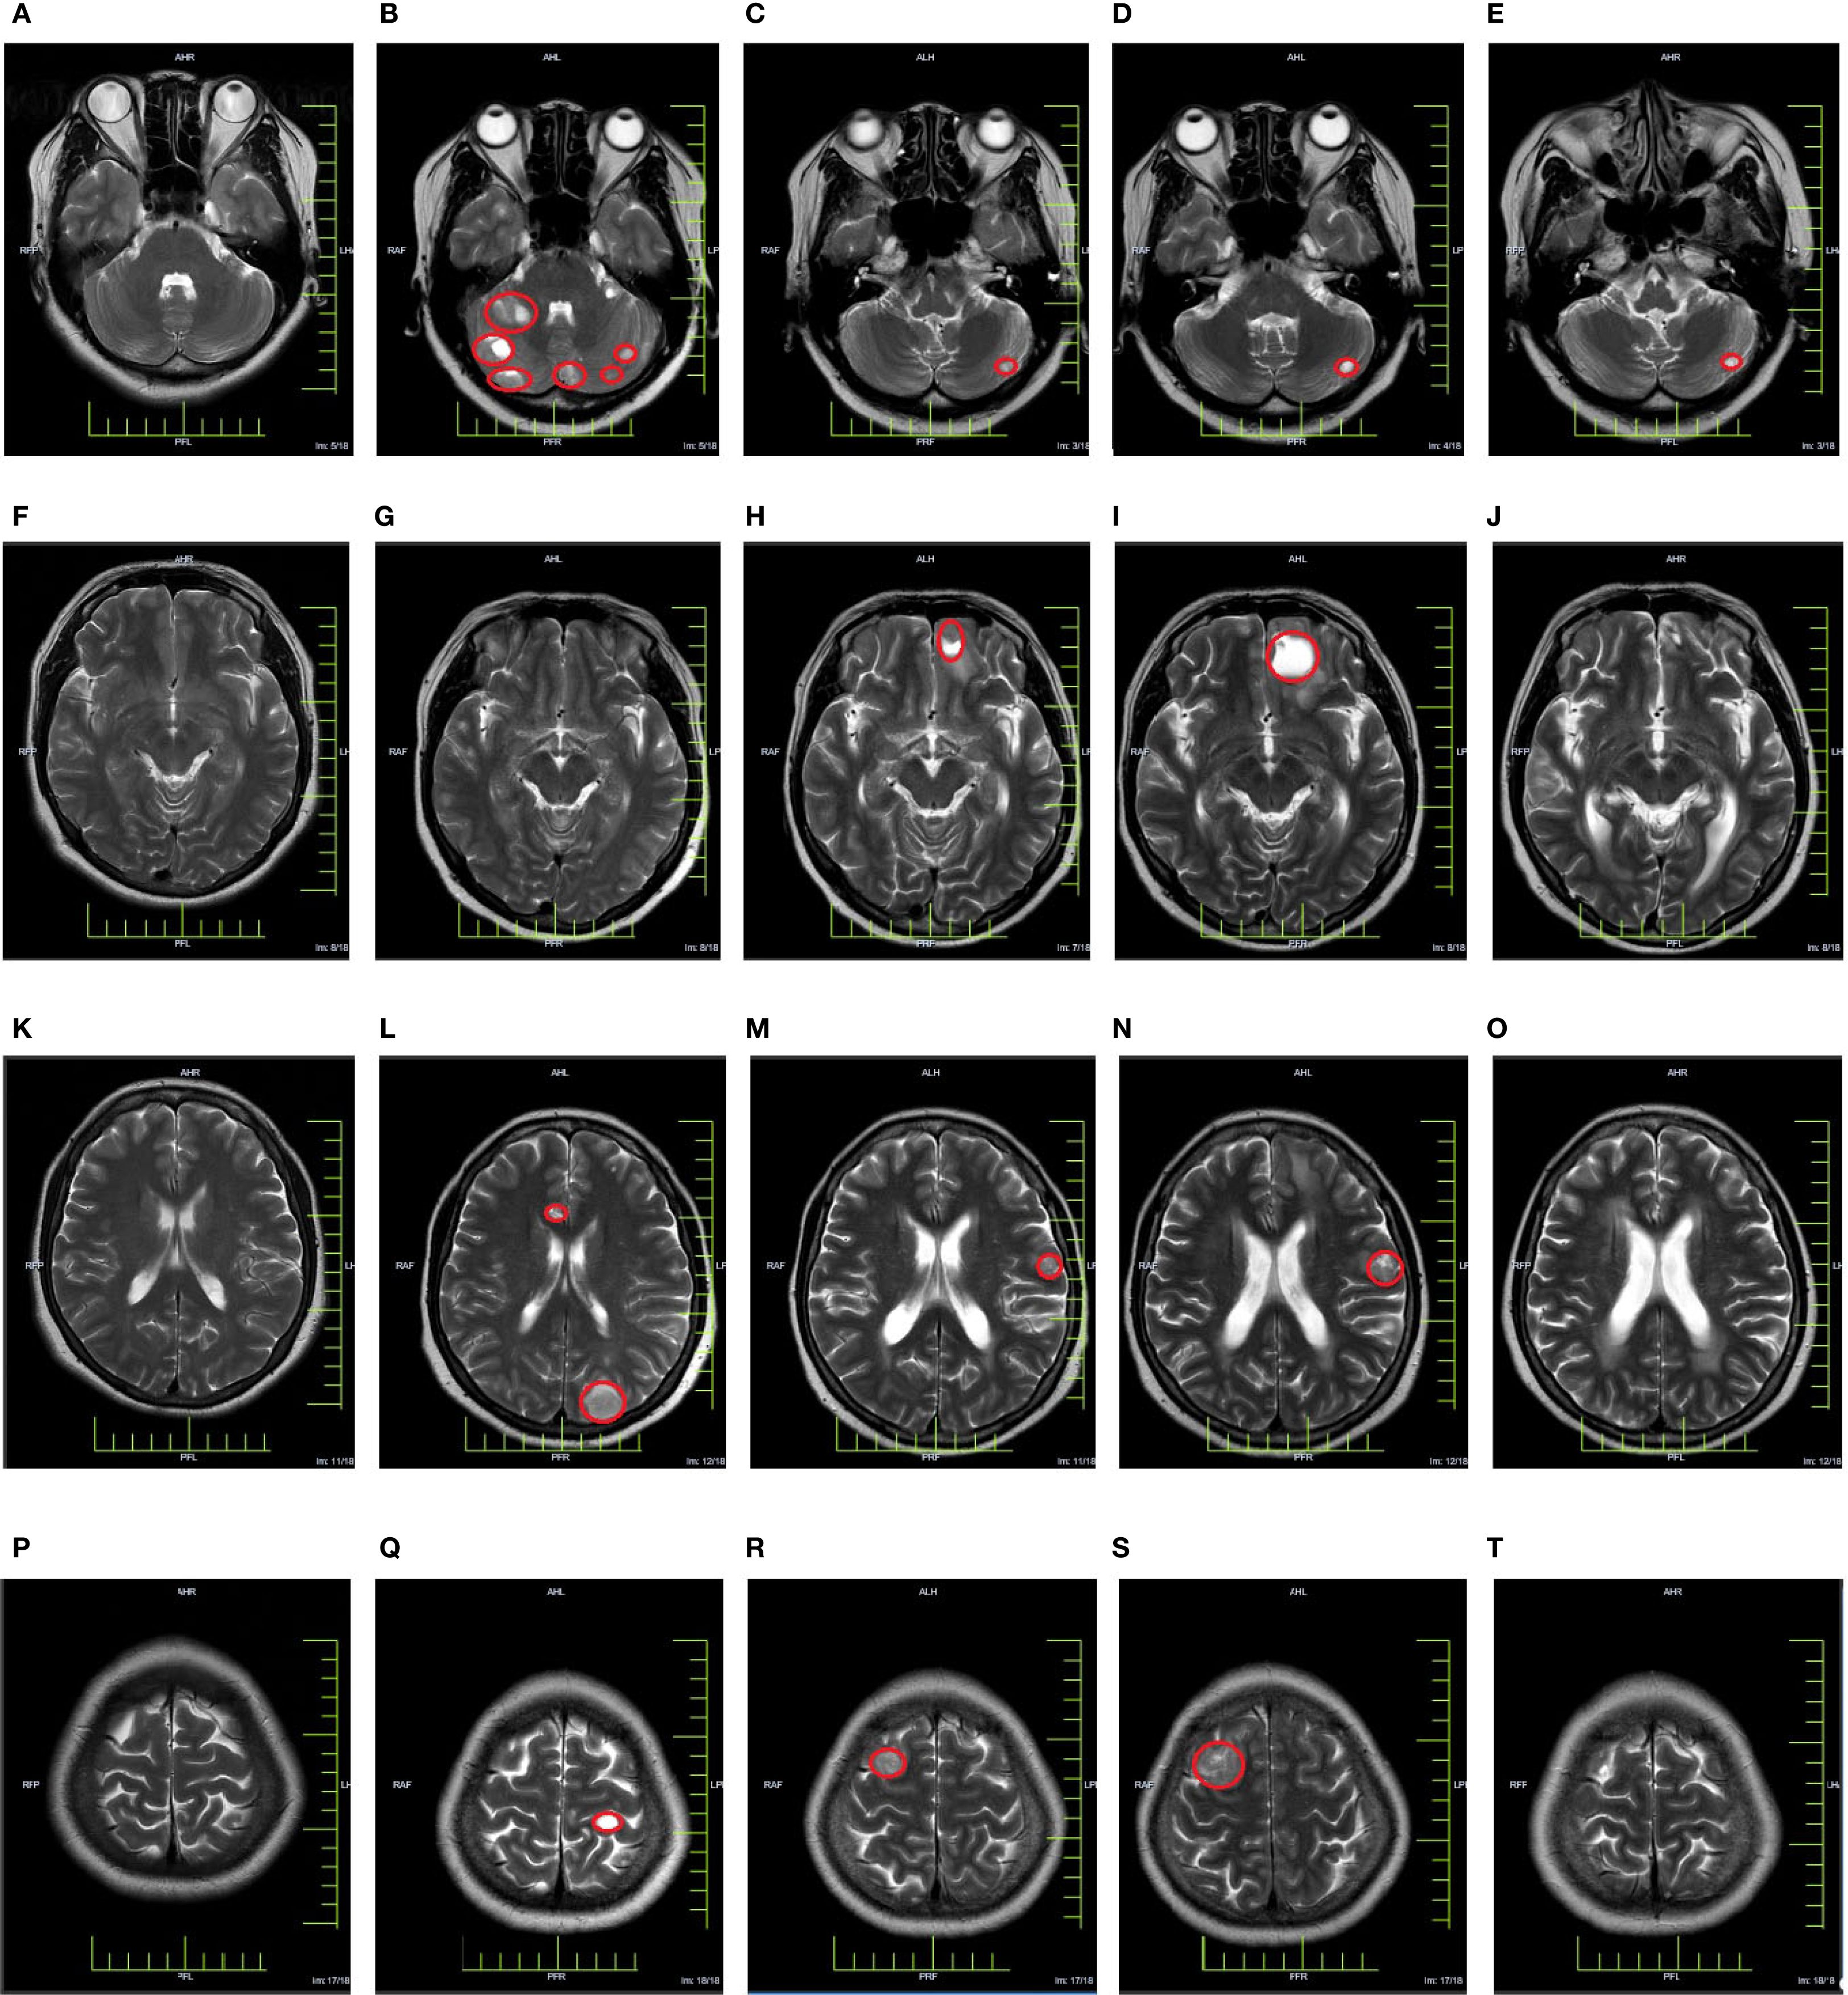

In March 2023, a subsequent MRI examination unveiled the emergence of newly developed intracranial metastases in the patient. Despite being offered immune combined system chemotherapy, the patient declined and expressed a preference to continue with oral chemotherapy medication. In October 2023, the patient experienced worsening symptoms of dizziness and headache. Subsequent examination revealed an enlargement of lesions in bilateral frontal and temporal lobes, while no progression was observed in other sites throughout the body. After extensive communication with the patient, she remained steadfast in her refusal of immunotherapy combined with systemic chemotherapy. However, she expressed willingness to undergo immunotherapy coupled with targeted therapy. Taking into account economic factors, the patient opted for off-label use of sintilimab and signed an informed consent. Consequently, her treatment regimen was formulated as a combination therapy involving sintilimab and bevacizumab. (bevacizumab 15 mg/kg, d1, ivgtt + sintilimab 200 mg, d1, Q3W). Encouragingly, CR was achieved following the assessment of 4 treatment cycles. Currently, the maintenance treatment has been maintained for a period of 16 months. Important imaging evaluations of this patient over 3 years are shown in Figure 2.

Figure 2. Cranial MRI evaluation map [(A, F, K, P) In March 2021, a baseline cranial MRI evaluation was performed, revealing no apparent abnormalities in the cranium. (B, G, L, Q) In March 2022, a follow-up cranial MRI examination was conducted, revealing the presence of multiple metastatic lesions. (C, H, M, R) In March 2023, a follow-up cranial MRI examination was conducted, revealing the presence of newly detected lesions in the cranium (D, I, N, S) In October 2023, a follow-up cranial MRI examination was performed, revealing an increasing trend in the size of the lesion. (E, J, O, T) In December 2023, a follow-up cranial MRI examination was conducted, revealing a significant reduction or disappearance of metastatic lesions].